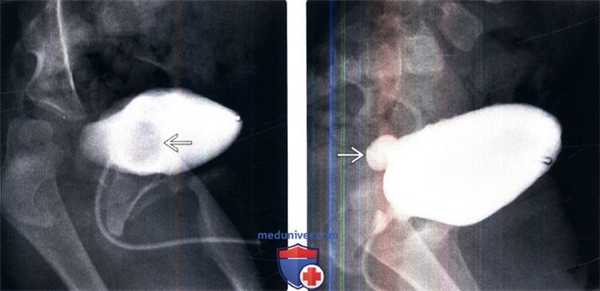

(Слева) МЦУГ в прямой косой проекции: у младенца мужского пола с анамнезом инфекции мочевыделительных путей определяется округлый дефект наполнения мочевого пузыря с гладкой поверхностью. Эти признаки характерны для уретероцеле.

(Справа) После дальнейшего растяжения мочевого пузыря уретероцеле вывернулось наружу из просвета мочевого пузыря. Выворот уретероцеле можно ошибочно принять за дивертикул мочевого пузыря.